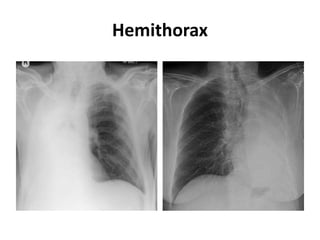

Hemithorax

Mediastinum pushed away from the opacified side

• Pleural effusion

• Large lung mass

• Diaphragmatic hernia

Mediastinum pulled toward the opacified side

• Total lung collapse

• Pneumonectomy

• Pulmonary hypoplasia/agenesis

Mediastinum remains central in position

• Consolidation

• Pleural/chest wall mass

• Combination of pathologies